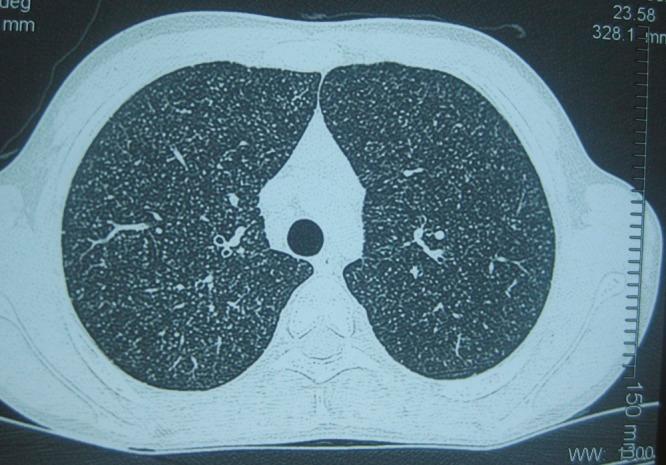

Persistent Fever and Skin Lesions Due to Histoplasmosis in a Boy from Rural Nepal.

Am J Trop Med Hyg. 2016 Feb;94(2):249-250. doi: 10.4269/ajtmh.15-0664.